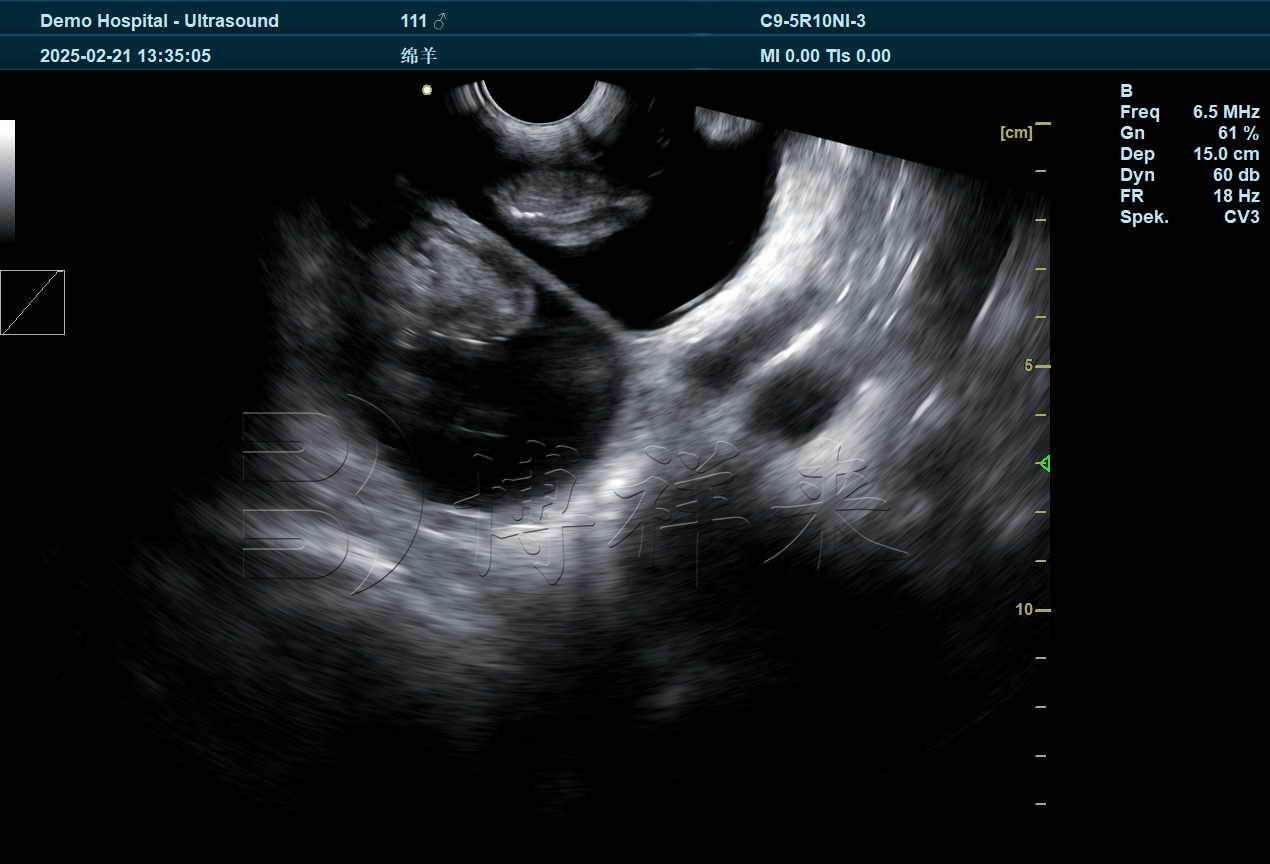

- 早期诊断(35-45天): 这是检测双胎的理想窗口期。此时胎儿尚未完全长大,羊水充盈,技术员可以在一个视野内或通过轻微移动探头观察到两个独立的胎囊及胎心搏动。

- 识别特征: 双胎影像: 屏幕上会出现两个清晰的圆形或椭圆形胎囊暗区,内部可见胚胎反射。

- 鉴别诊断: 需注意区分双胎与子宫内的褶皱或尿道影像。博祥来设备的灰阶显示较为细腻,有助于技术员分辨胎儿的胎心搏动。